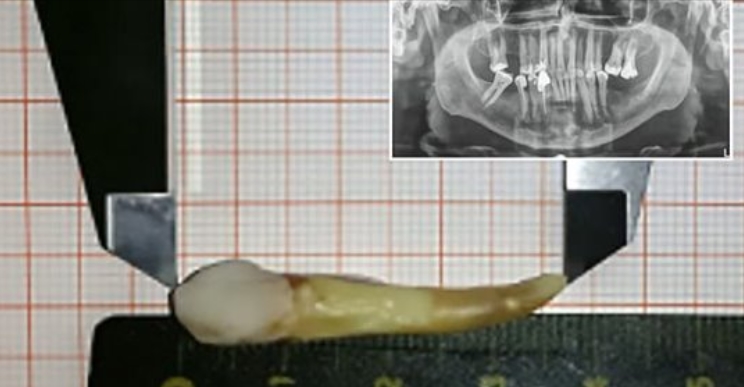

سجلت موسوعة “غينيس” للأرقام القياسية نجاح طبيب بمدينة أوفنباغ الألمانية في اقتلاع سن بلغ طوله 37.2 ميليمتر، ما يجعله أطول سن بشري.

وتسلم الطبيب الألماني، ماكس لوكاس، شهادة من موسوعة “غينيس” لاقتلاعه السن.